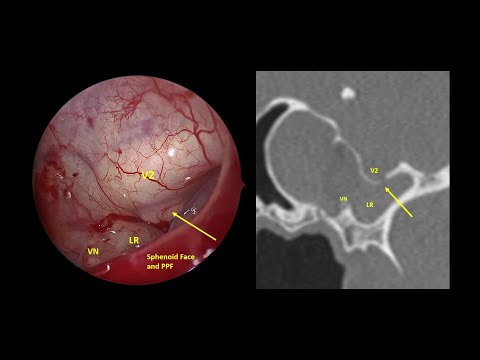

Kevin C. Welch, MD

Professor Rhinologist, sinus surgeon and skull base surgeon. Wine Guy. WSET II, FWS, Rhône ML, Bordeaux ML #revisionsinussurgery #polyps #sinussurgery